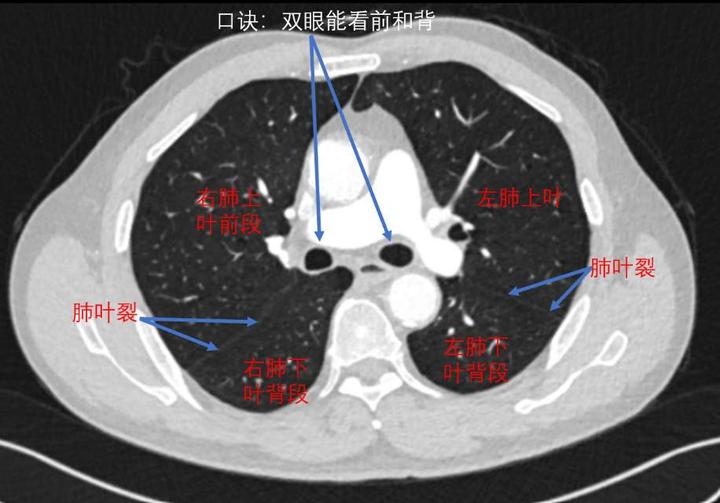

横断位左肺借斜裂成上,下两叶;右肺借斜裂和水平裂成上,中和下叶三叶.

上叶后段支气管的层面1首先,我们来看一位患者高分辨胸ct的肺窗连续

心脏层面:部分上叶和大部分下叶的各个基底段4肝脏层面:右肺下叶和左

复习基础知识右肺上叶:s1:尖段;s2:后段;s3:前段.

左肺: s4 上叶上舌段 s5 上叶下舌段 s6 下叶背段 第29页